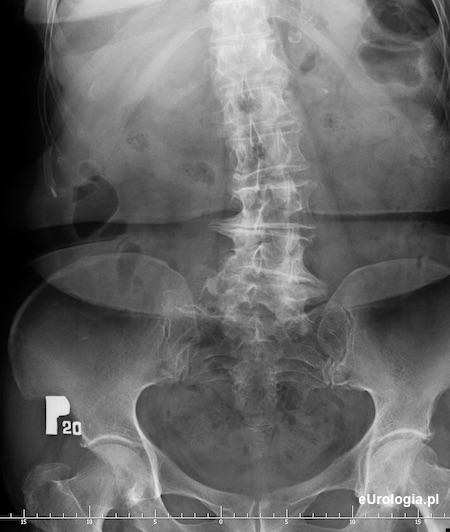

Kamica górnego odcinka moczowodu - urografia

Cień wapienny 11x8 mm na wysokosci wyrostka poprzecznego L5 po stronie prawej mogacy byc złogiem w górnym odcinku prawego moczowodu